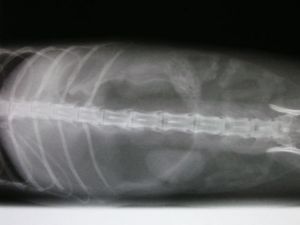

The duty vet felt her stomach and – lo and behold – actually could feel something which she thought was, indeed, a blockage. They X-rayed Snoopy and came back to show us this whacking great object which was stopping up her guts.

The vet had to call the specialist surgeon into the surgery to do the operation! Fortunately it all went well but she had to stay in hospital for 5 days, because they wanted to make sure there were no complications, as the build-up of noxious gasses in her stomach during the blockage had been cause for concern.